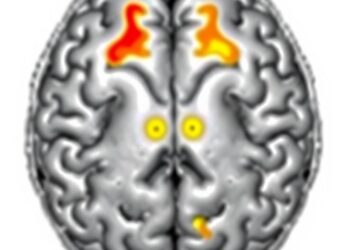

A laboratory controlled experiment including both healthy adults and adults with coronary artery disease (CAD) found that passive heat exposure was enough to increase myocardial blood flow (MBF) in all participants, regardless of age and health status, creating significant stress on the heart. The authors observed asymptomatic heat-induced myocardial ischemia in some participants with CAD, suggesting that these adults may benefit from minimizing cardiac strain during extreme heat by staying cool. The study is published in Annals of Internal Medicine.

Researchers from the Montreal Heart Institute conducted an experimental study comprised of 20 healthy young adults, 21 healthy older adults, and 20 older adults with CAD to quantify the MBF requirements of heat exposure. In a laboratory setting, participants were heated until their core temperature increased 1.5 degrees Celsius (C), and their MBF was measured before exposure and at every increase of 0.5 degrees C to their core temperature. The authors found that MBF increased in all participants when their body temperature increased by 1.5 degrees C. The authors additionally observed that 7 participants with CAD experienced asymptomatic heat-induced myocardial ischemia based on imaging evidence.